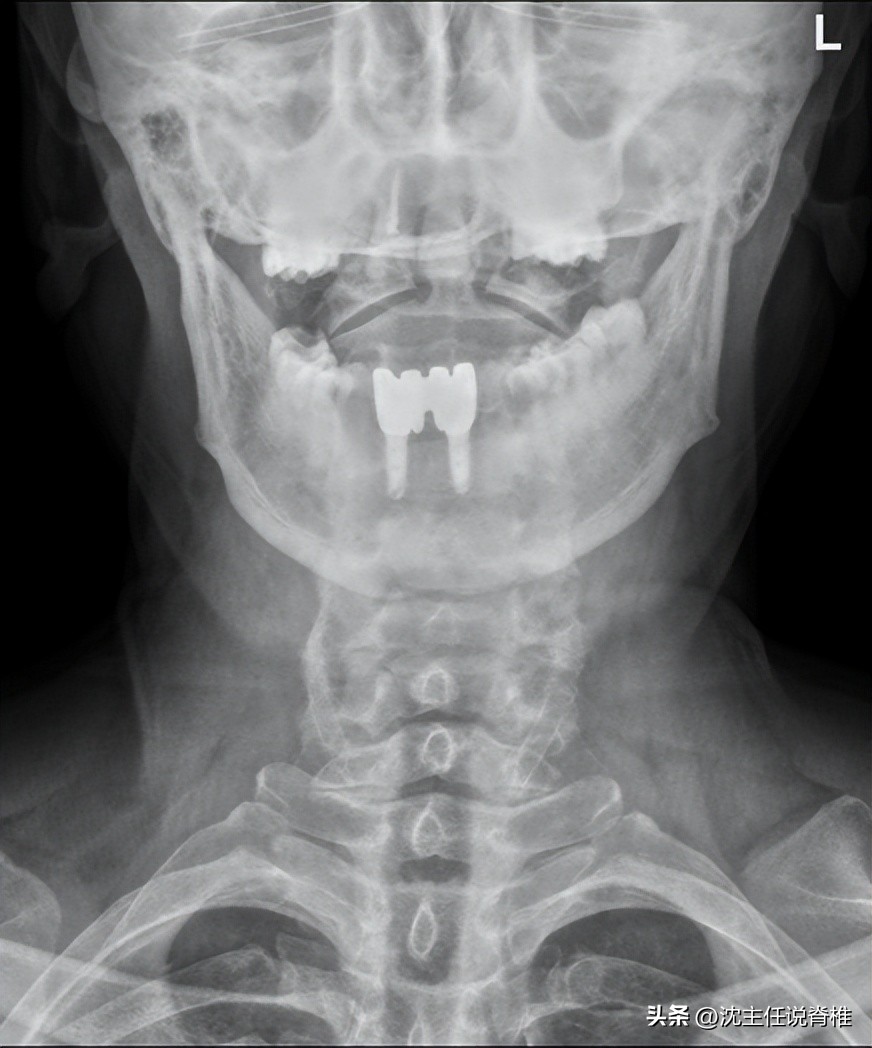

我在给易先生做体格检查的时候,发现他的颈椎第二、三关节突关节是有 明显错位 的,这种情况和耳鸣的表现有关系,上段颈椎的错位会 影响 到部分的 神经和血管 ,压迫时间久了有可能会导致耳鸣症状的出现。另外附着在附近的斜角肌、胸锁乳突肌和枕下肌群也是有较明显的 张力增高 的情况。